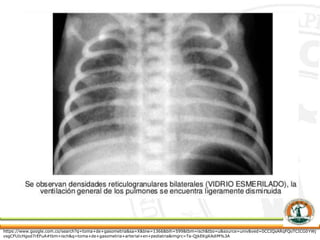

 Una radiografía de tórax muestra que los

pulmones tienen una apariencia de “vidrio molido”,

que a menudo se desarrolla de 6 a 12 horas

después de nacer.

Rayos X de tórax mostrando

hiperinflación con diafragma aplanado

y atelectasias bilaterales en un recién

nacido de 16 días.